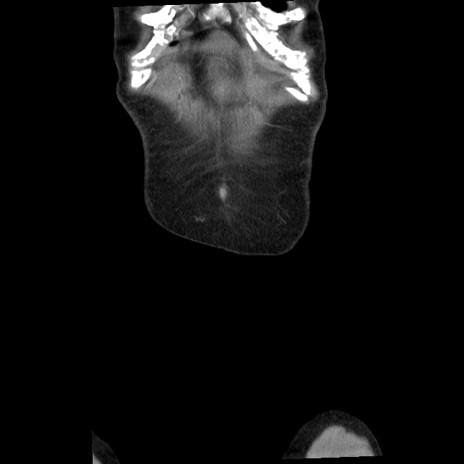

症例1(冠状断像)

【症例】80歳代女性

【主訴】腹痛

【現病歴】8時間前から腹痛あり来院。

【既往歴】糖尿病、脂質異常症、子宮体癌にて子宮全摘術

【身体所見】意識清明・会話良好だが腹痛で苦悶様、全腹部にわたって反跳痛と圧痛あり

【データ】WBC 13600、CRP 0.14、LDH 224、CK 90